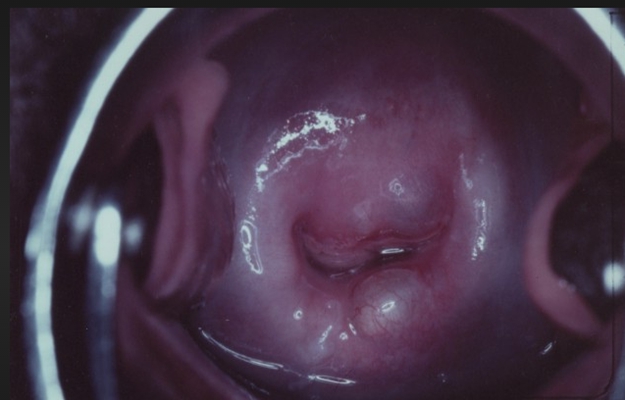

子宮頸癌前病變圖片

宮頸癌的早期症狀

宮頸癌的早期症狀

宮頸癌的早期症狀

宮頸癌的早期症狀

宮頸癌的早期症狀

宮頸癌的早期症狀

宮頸癌的早期症狀

宮頸癌的早期症狀

宮頸癌的早期症狀

宮頸癌的早期症狀